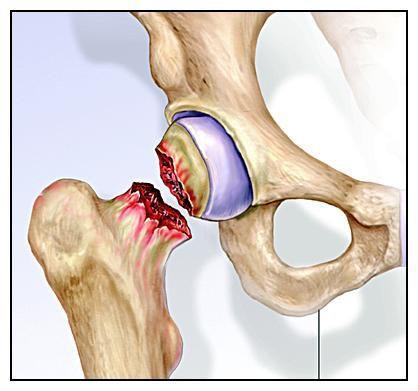

股骨头坏死的三道"预警防线"

图片尺寸2048x1879